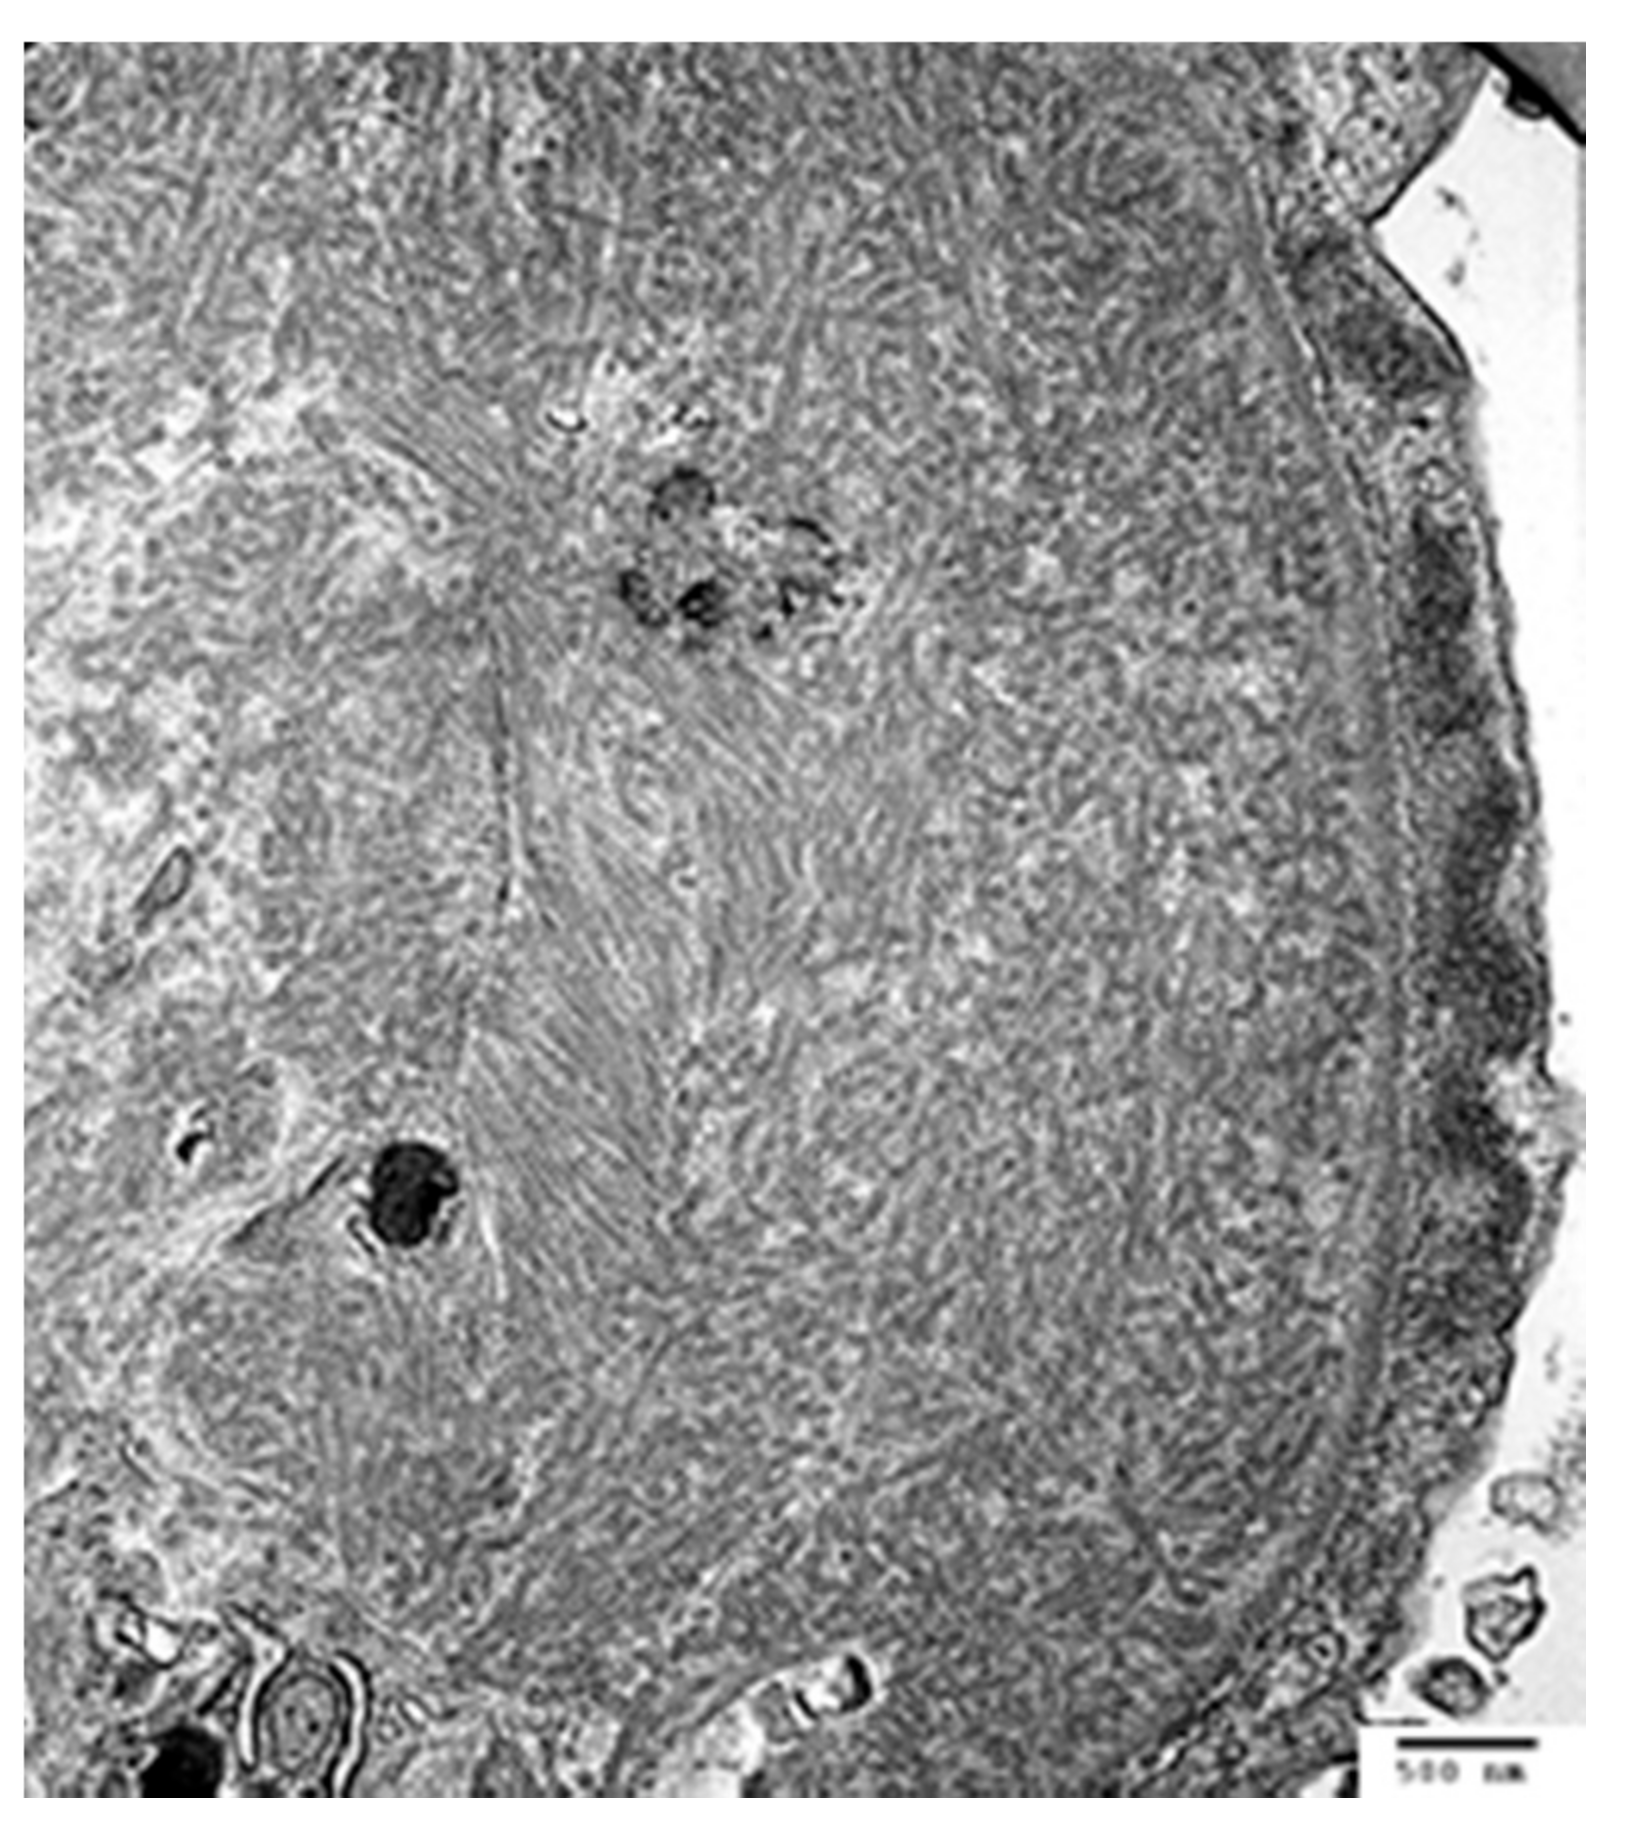

| Immunotactoid glomerulopathy | Endocapillary to MPGN pattern, membranous | 66% monoclonal, often IgG1 kappa | Fibrils with hollow cores and parallel arrays, ~30 nm | Exclude cryoglobulinemia. IgG subclasses confirm IgG monoclonality. DNAJB9 negative | Unknown |